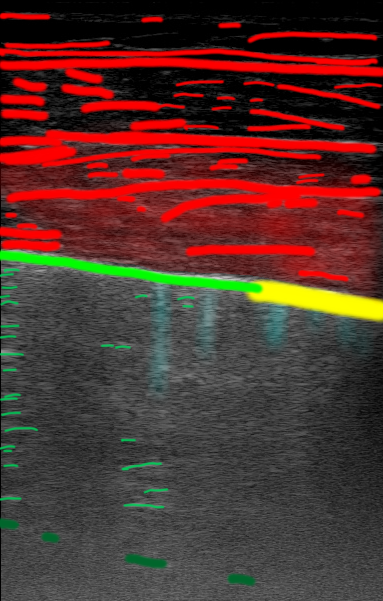

Figure 1 is an example segmentation label, thresholded by confidence to show the distribution of confidences in a single example. As the confidence threshold increases, the resulting segmentation labels get more refined. However, there may be a loss of features in the labels once the thresholds get sufficiently higher than the expert’s confidence in that feature’s appearance. For example, vertical lines disappear once the threshold becomes 40% in Figure 1. By thresholding the confidence labels this way and conducting further analysis with downstream tasks, we can gain a sense of how prominent these LUS features need to be for them to be clinically relevant.

| LUS Image | Soft Label | |||||||

|---|---|---|---|---|---|---|---|---|